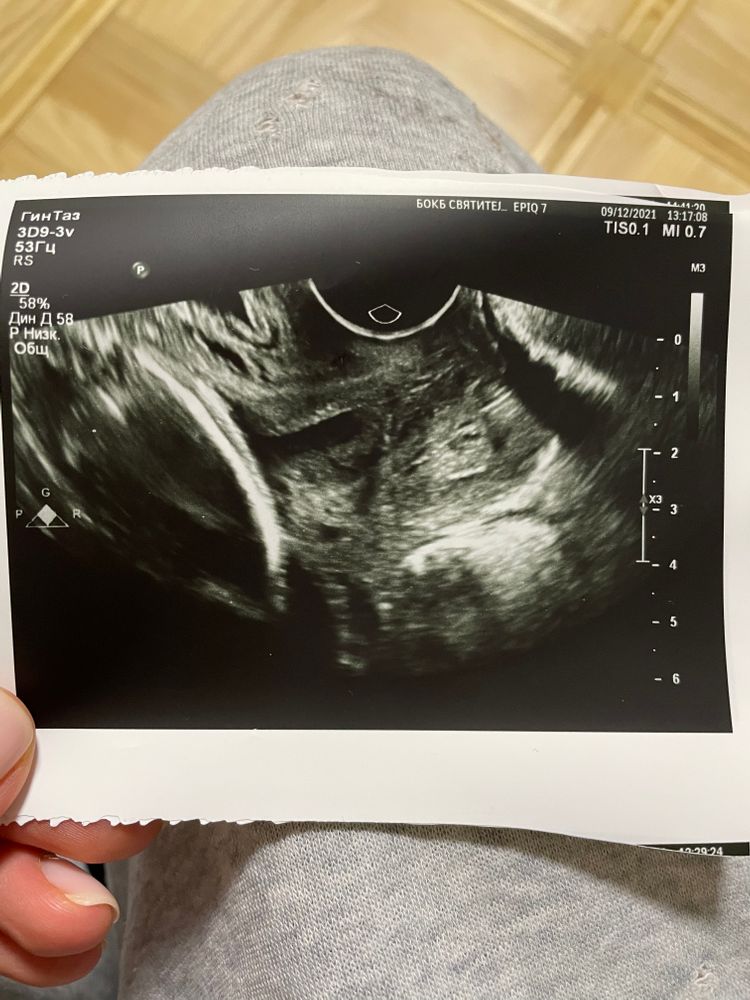

Ромашка, есть🙏🏽Первое фото в 24 недели, второе фото в 28.3 недели в 26 она мне фото не давала

квитка, я, конечно, не врач.. Но цервикометрий в своей жизни сделала штук 40.

Визуально не очень выглядит. Зев все таки больше U, чем T.

По всяким их протоколам после 26 нед диагноз Ицн не правомочен. Но вы молодец, что мониторите. Я думаю, что вы спокойно доносите, тк с 24 нет отрицательной динамики. Но обязательно держите на контроле дальше.